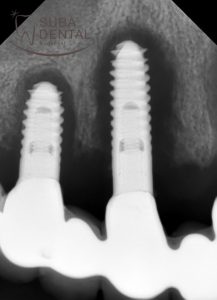

Precíziós lenyomat a 2 darab Straumann implantátumról a zárt kanalas lenyomatvételi fejekkel (oldalnézetből)

A kezelés során eltávolítjuk a régi implantátum koronát vagy hidat, precíziós lenyomatokat veszünk, és a mesterminta elkészítése után tudja csak a technikus megrendelni az egyénre szabott implantátum felépítményeket (abutment), amire elkészül az új korona vagy híd. Rendelőnk csak akkor tud garanciát vállalni az új fogpótlásra, ha minden új felépítményekre készül!